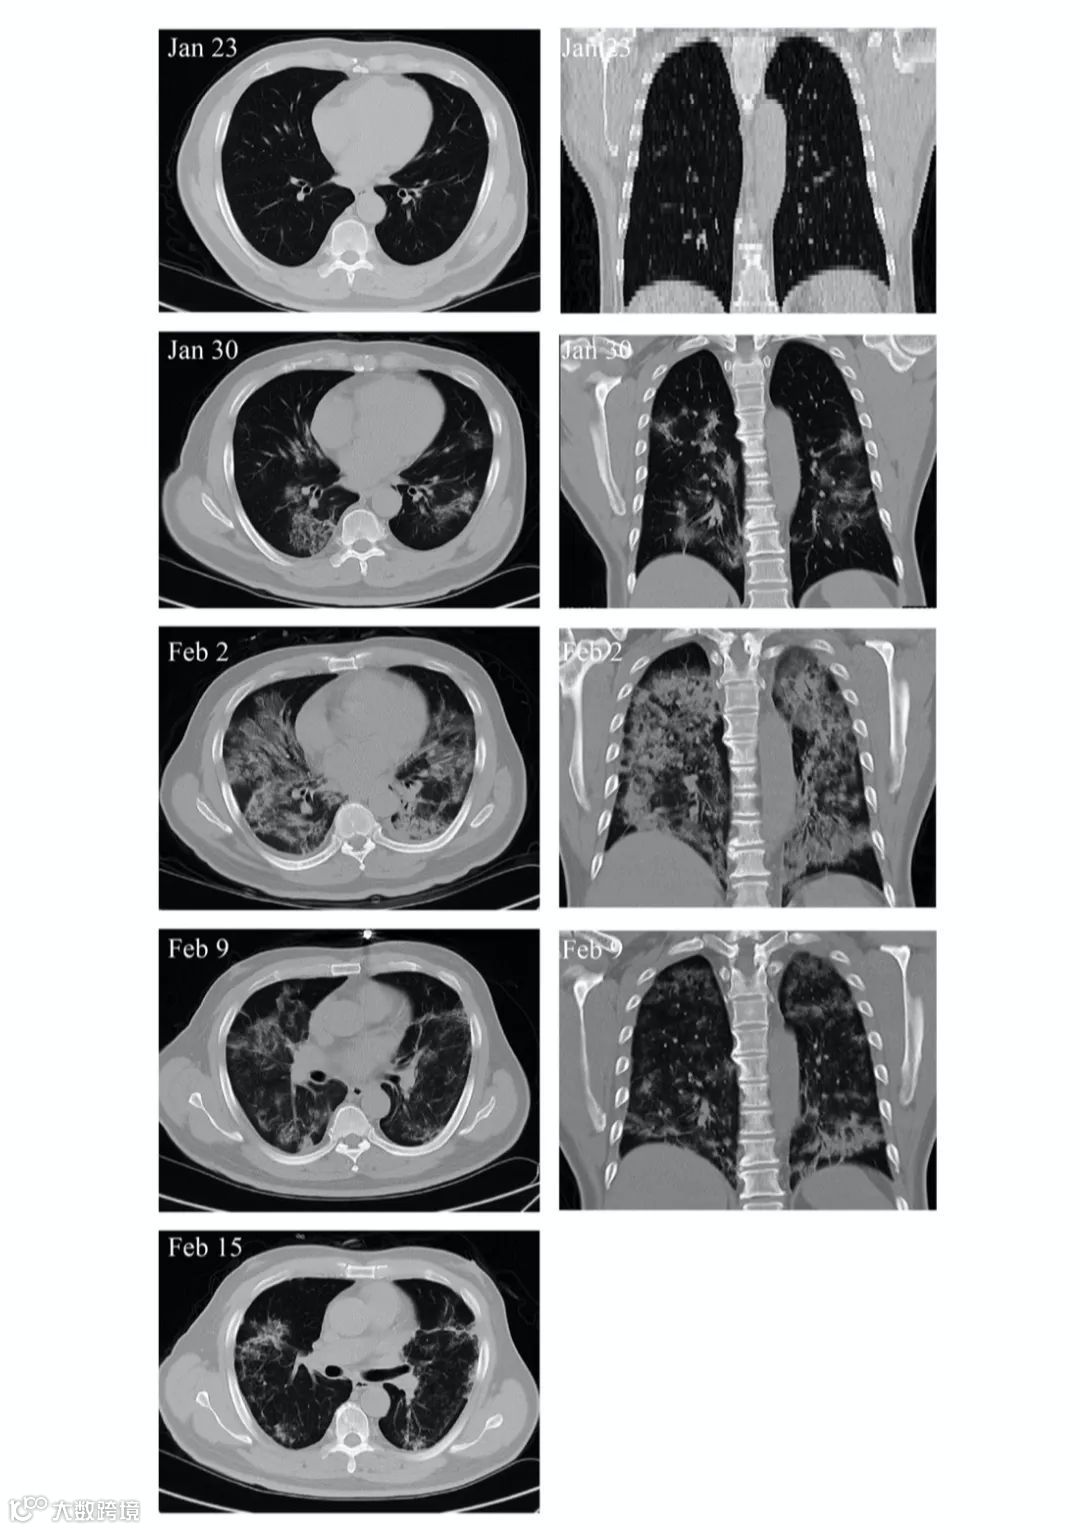

另外,MSC移植能显著加快治疗进程。移植后4天,新冠肺炎危重症患者呼吸频率降至正常范围、发烧和呼吸急促等症状消失。移植后9天,胸部CT成像显示毛玻璃样混浊和肺炎浸润已大大减少。

✎ 危重患者肺部影像学显示症状改善